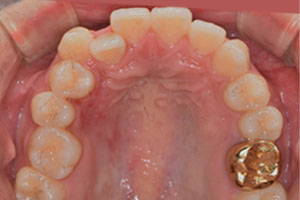

치료증례 전후사진

Before & After